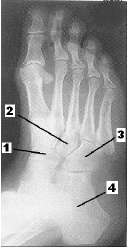

Após analisar atentamente a figura abaixo, responda à questão.

A imagem acima corresponde a uma incidência em

A

oblíqua AP – rotação medial.

B

perfil médio-lateral.

C

AP com carga.

D

AP.